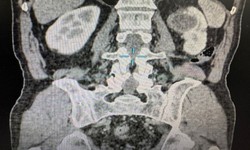

Camera bệnh viện - 09/05/2023 12:45SKĐS - 3 năm trước bệnh nhân thực hiện nội soi niệu quản trái tán sỏi, tuy nhiên 6 tháng gần đây bệnh nhân lại đau vùng thắt lưng trái, đau âm ỉ, đi khám phát hiện bị mắc ung thư biểu mô tế bào sáng của thận độ 1.